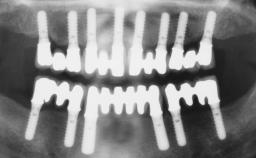

Rehabilitating an Edentulous Maxilla with a Fixed Dental Prosthesis Following Provisional Immediate Loading

This case features the flapless computer-guided placement of 7 bone-level implants, distributed to provide maximal support for the prosthetic framework. A rigid one-piece metallic framework was utilized as an interim restoration to reduce the risk of fracture associated with this prosthetic design. As part of the clinical examination, the SAC Assessment Tool was used, resulting in a surgical and restorative risk classification as “complex”.

# of Implants 7

Type of Implants Two-Piece

Guided Surgery Yes

SAC Level Complex

Defining Characteristics Fully edentulous upper jaw to be rehabilitated with four or more implants

Modality 6+ implants with immediate loading